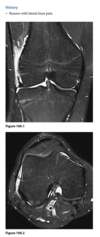

Q

39 yo man fall

Axial T2 fat sat MR - bone contusions in medial patella and lateral femoral condyles (Arrows) with associated tear of medial retinaculum (Arrowhead)

Diagnosis: Acute patellar dislocation relocation

Occurs with internal rotation of femur on fixed and externally rotated femoral condyle - bone contusions on both.

Due to direct impaction, associated with ACL tears.

Radiographs = Lipohaemarthrosis or chip fracture adjacent to donor site of medial facet of patella.

MR findings = Disruption or sprain of the medial retinaculum, lateral patellar tilt or subluxation, lateral femoral condylar and medial patellar osseous contusions. Osteochondral injury to medial patella or lateral femur.